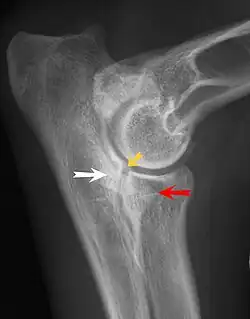

Elbow dysplasia

Ununited anconeal process

UAP is caused by a separation from the ulna of the ossification center of the anconeal process.[7] FMCP is caused by a failure of the coronoid process to unite with the ulna.

Diagnosis is through x-rays, arthroscopy or CT (computed tomography). In cases with significant lameness, surgery is the best option, especially with UAP. However, conservative treatment is often enough for cases of FMCP and OCD of the medial humeral epicondyle. The dogs are exercised regularly and given pain medication, and between the ages of 12 and 18 months the lameness will often improve or disappear.[4] Control of body weight is important in all cases of elbow dysplasia, and prevention of quick growth spurts in puppies may help to prevent the disease.

Surgery for FMCP consists of removal of cartilage and bone fragments and correction of any incongruity of the joint. Reattachment of UAP with a screw is usually attempted before the age of 24 weeks, and after that age the typical treatment is removal of the UAP.[8] Without surgery, UAP rapidly progresses to osteoarthritis, but with FMCP osteoarthritis typically occurs with or without surgery. Osteoarthritis is also a common sequela of OCD of the humerus despite medical or surgical treatment.[8] Elbow replacement surgery has been developed and can be an option for treatment.[9]